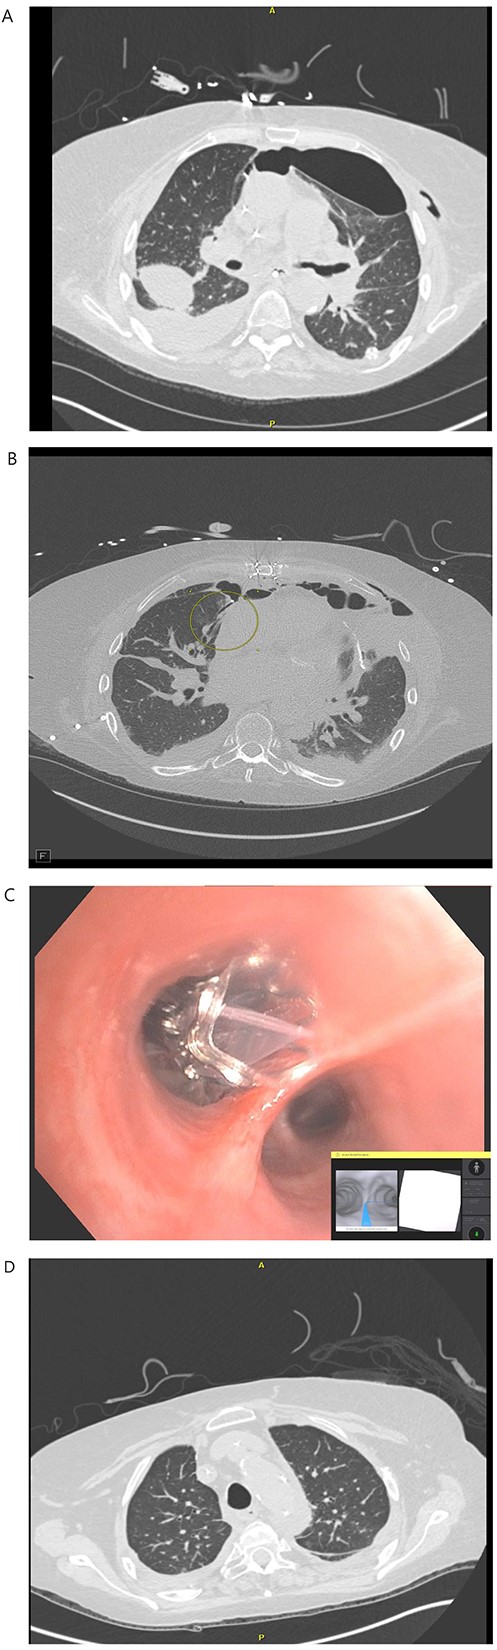

A 71-year-old female with end-stage lung failure underwent a bilateral lung transplant with wedge resection of the right middle lobe and left lingular of donor lungs using Endo-GIA staplers due to oversized lungs. On postoperative day (POD) 21, a BPF was noticed from the right middle lobe at the staple line (Fig. 1B) with persistent bilateral pneumothorax and a loculated right-sided pleural effusion (Fig. 1A) on chest computed tomography (CT) scan that failed conservative treatment with multiple chest tubes. The patient underwent RAB-assisted BPF for closure of BPF on POD 35 using IonTM Endoluminal System. RAB was used to locate and reach the medial lobe bronchial segment of the right middle lobe (Fig. 1C), and a combination of Histoacryl and lipiodol were instilled. The RAB system was then withdrawn, and traditional bronchoscopy was used to deploy the Zephyr® endobronchial valve (Pulmonx, Redwood City, CA) in the medial segment bronchus. An uneventful recovery after the procedure with an improved CT chest (Fig. 1D) was noticed and eventually discharged on POD 57. The EBV was removed on POD 133. At the last follow-up 1-year post transplant, the patient can carry out her daily activities at home without oxygen support.

(A) POD 21 BL pneumothorax and R pleural effusion. (B) POD 31 BPF with medial segment RML with BL pneumothorax and R hydropneumothorax. (C) POD 35 placement of endobronchial valve in medial segment of RML. (D): POD 41 resolution of BPF, pleural effusion and pneumothorax.